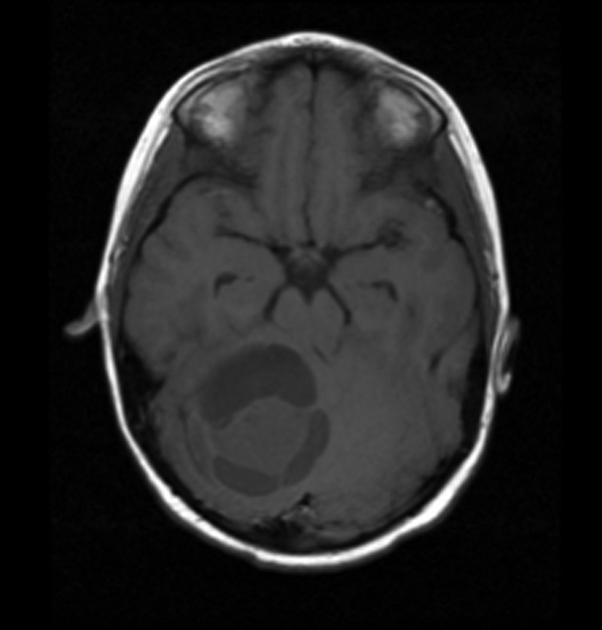

History and physical exam and CNS imaging are the primary work ups. In particular ask about NF-1. NF-1 patients are predisposed to optic pathway tumors and may have astrocytic tumors in other parts of the CNS. Pilocytic astrocytomas have unique imaging with a well circumscribed mass, frequently with a cystic component that may be large relative to the size of the tumor solid component. The solid component enhances brightly on T1/gad sequences and there is little edema or mass effect. Diffuse of fibrillary astrocytomas are not well seen on non-contrast enhanced CT or T1-MRI. The are seen well on T2/FLAIR imaging which best illustrates the extent of disease.

T1 without gadolinium

T1 with gad

T2 pilocytic astrocytoma